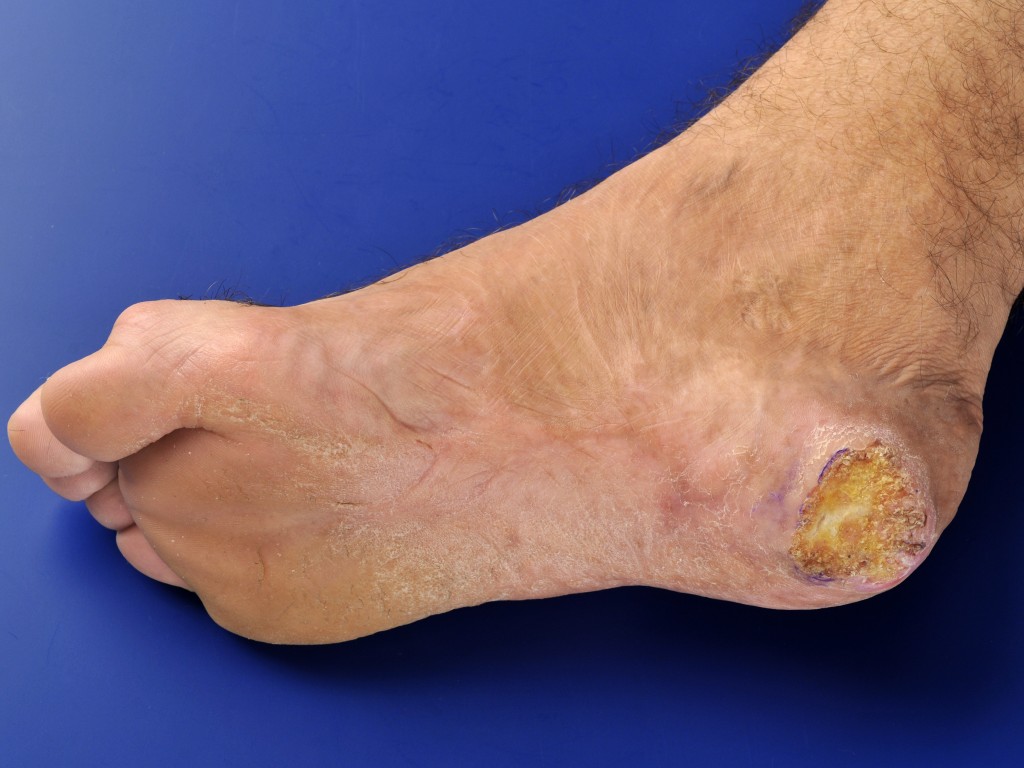

![Verruceus carcinoom van de hiel (click on photo to enlarge) [source: www.huidziekten.nl] Verruceus carcinoom van de hiel](../../../images/verruceus-carcinoom-hiel-1z.jpg) |

![Verruceus carcinoom van de hiel (click on photo to enlarge) [source: www.huidziekten.nl] Verruceus carcinoom van de hiel](../../../images/verruceus-carcinoom-hiel-2z.jpg) |

![Verruceus carcinoom van de hiel (click on photo to enlarge) [source: www.huidziekten.nl] Verruceus carcinoom van de hiel](../../../images/verruceus-carcinoom-hiel-3z.jpg) |

| verruceus

carcinoom |

verruceus

![Verruceus carcinoom van de hiel (click on photo to enlarge) [source: www.huidziekten.nl] Verruceus carcinoom van de hiel](../../../images/verruceus-carcinoom-hiel-4z.jpg) |

| excisie

voor PA |